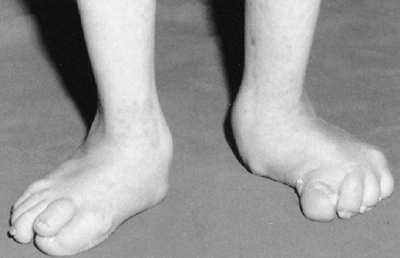

Angular malformations of the lower extremities, especially genu valgum,

are common. Because the genu valgum is often associated with restricted

range of motion, flexion contractures, and pain in the joints, it is

postulated that an intraarticular growth disturbance contributes to the

angular malformation. Hip abnormalities that show up in

roentgenographic tests, acetabular dysplasia for example, are

frequently discovered in asymptomatic patients. Deformities in the

hindfoot are frequent and are usually heel valgus, but congenital

equinovarus and “Z-foot” deformities have also been described (173,176).